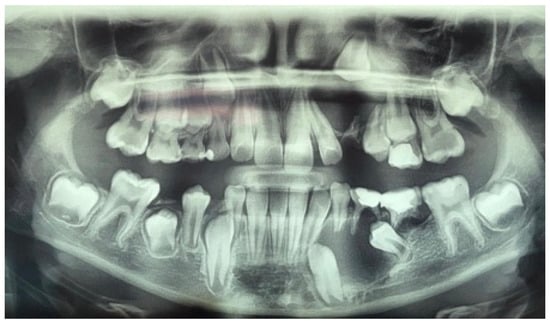

A panoramic radiograph and cone beam computed tomography (CBCT) showed a well-defined unicystic radiolucency extending from the left maxillary second incisor to the primary second molar on the same side. The permanent canine was impacted toward the maxillary sinus, and the root of the second incisor was tilted mesially by the lesion. Another radiolucency extended from the left lower lateral incisor to the primary second molar. Hypodontia of the permanent premolar was noted. The lesion was in contact with the inferior alveolar nerve [Figure 1].

Figure 1. Preoperative panoramic radiograph of a ten-year-old boy showing unicystic radiolucencies on the left side of the maxilla and mandible.